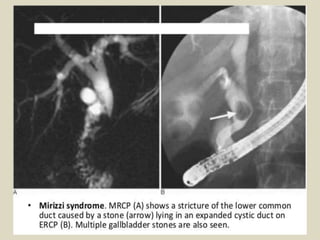

Mirizzi syndrome is produced by a gallstone impacting

either in the neck of the gallbladder or within the cystic

duct and secondarily obstructing the hepatic duct. The

initial classification of a gallstone either simply

compressing adjacent bile ducts as part of an acute

episode or a cholecystocholedochal fistula forming on a

chronic basis was subsequently expanded to include: Type

I: hepatic duct stenosis due to a stone impacting in the

cystic duct or gallbladder neck. This is the most common.

Type II: hepatic duct fistula due to a stone impacting in the

cystic duct or gallbladder neck. Type III: hepatic duct

stenosis due to a stone at the duct confluence. Type IV:

hepatic duct stenosis as a complication of cholecystitis and

no impacted calculus.

Mirizzi syndrome.

Mirizzi syndrome. a: Oblique coronal T2-weighted sequence. b: MRI cholangiography

with volume rendering. In this case, the presence of impacted gallstone in the cystic duct,

causing dilatation of the biliary tract and compression of the common hepatic duct.